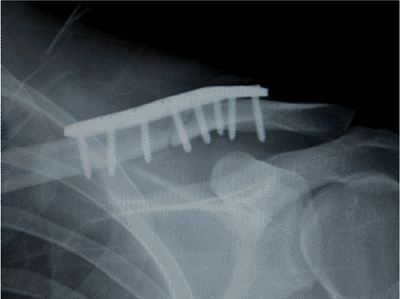

![]() |

|

Figure 1.20.

Postoperative radiograph demonstrating correction of the deformity, apposition of the bone ends, and accurate placement of the plate. |